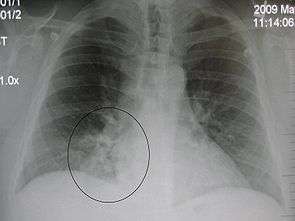

| A chest X-ray showing a very prominent wedge-shape bacterial pneumonia in the right lung. | |

AP CXR showing left lower lobe pneumonia associated with a small left sided pleural effusion

AP CXR showing right lower lobe pneumonia